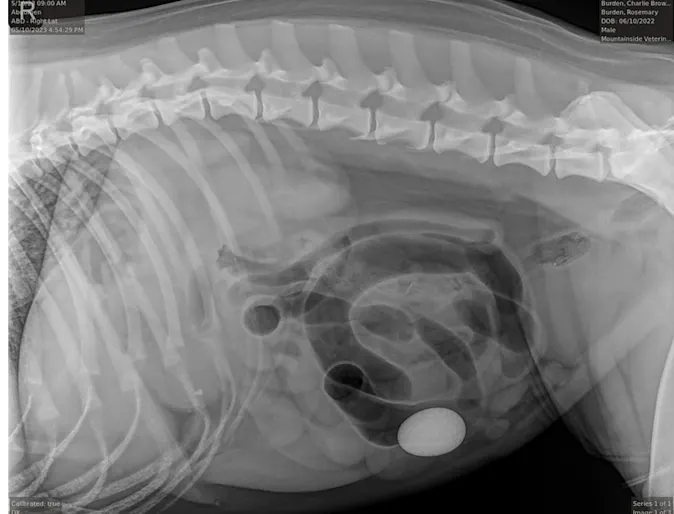

September 2023: Charlie Brown

Case Study

Good Grief! Charlie Brown presented to Mountainside Animal Emergency & Specialty when his owners noticed that he had ongoing vomiting and a decreased appetite.